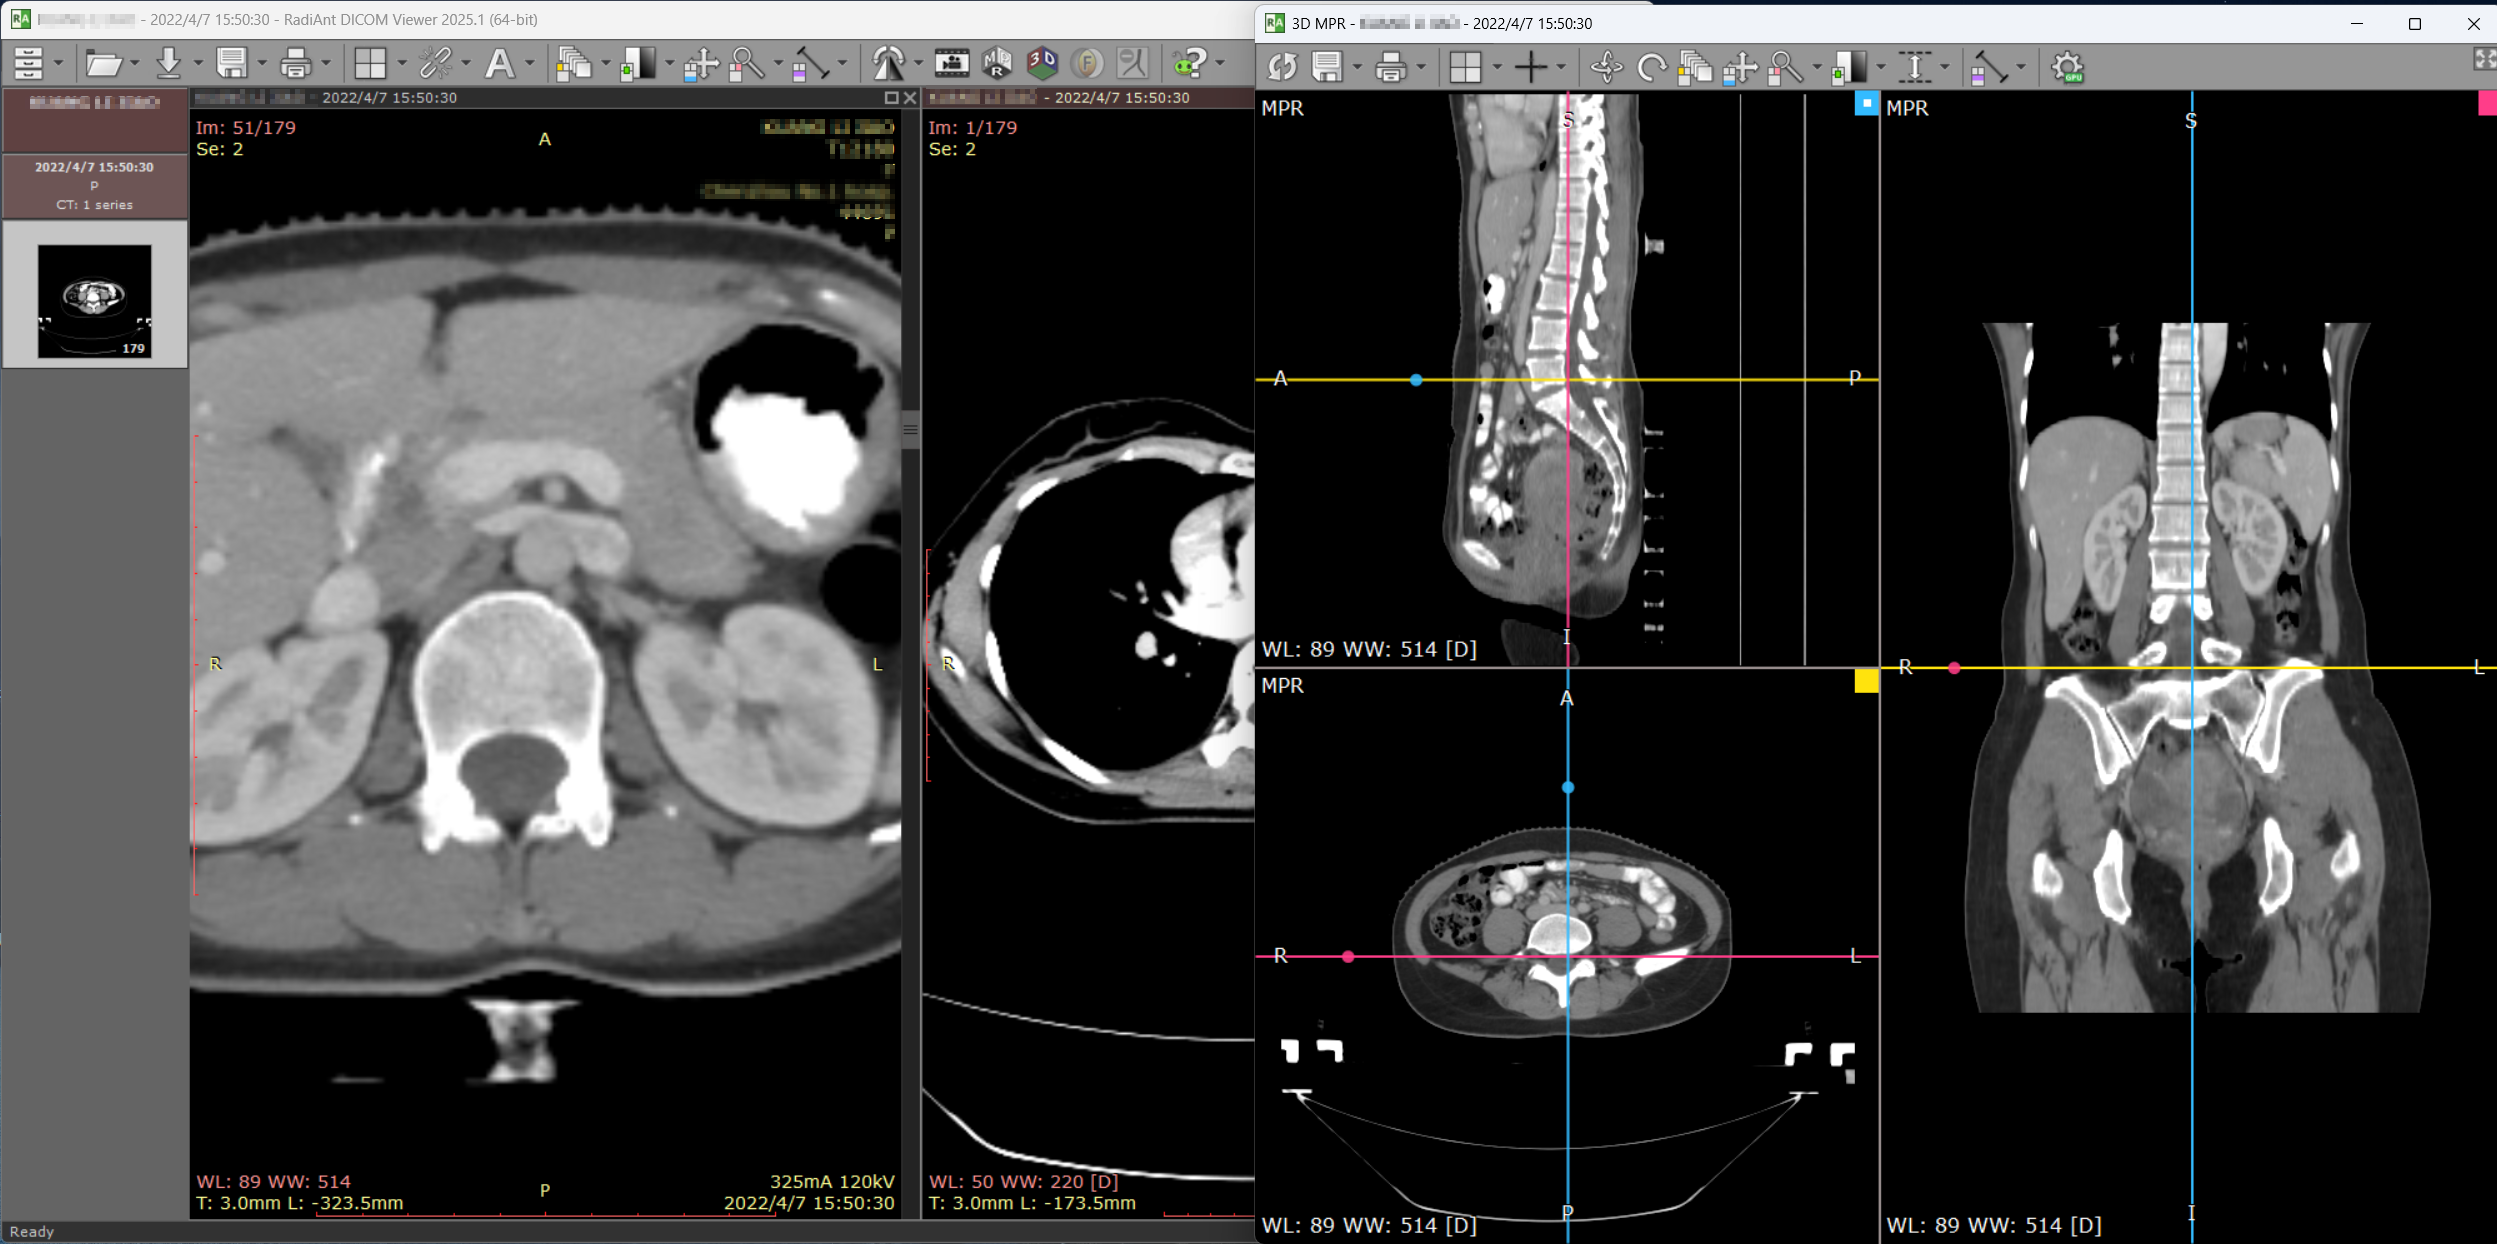

1. RadiAnt DICOM Viewer

- 影像专业从业者都知道的大名鼎鼎的软件,功能齐全,蚂蚁,永远滴神!

- 支持MPR、VR、3D虚拟、多维编辑、PET融合、DSA/超声动态DICOM视频

- 可对接医院的大型PACS系统,也可作为小型诊所的单机PACS服务器